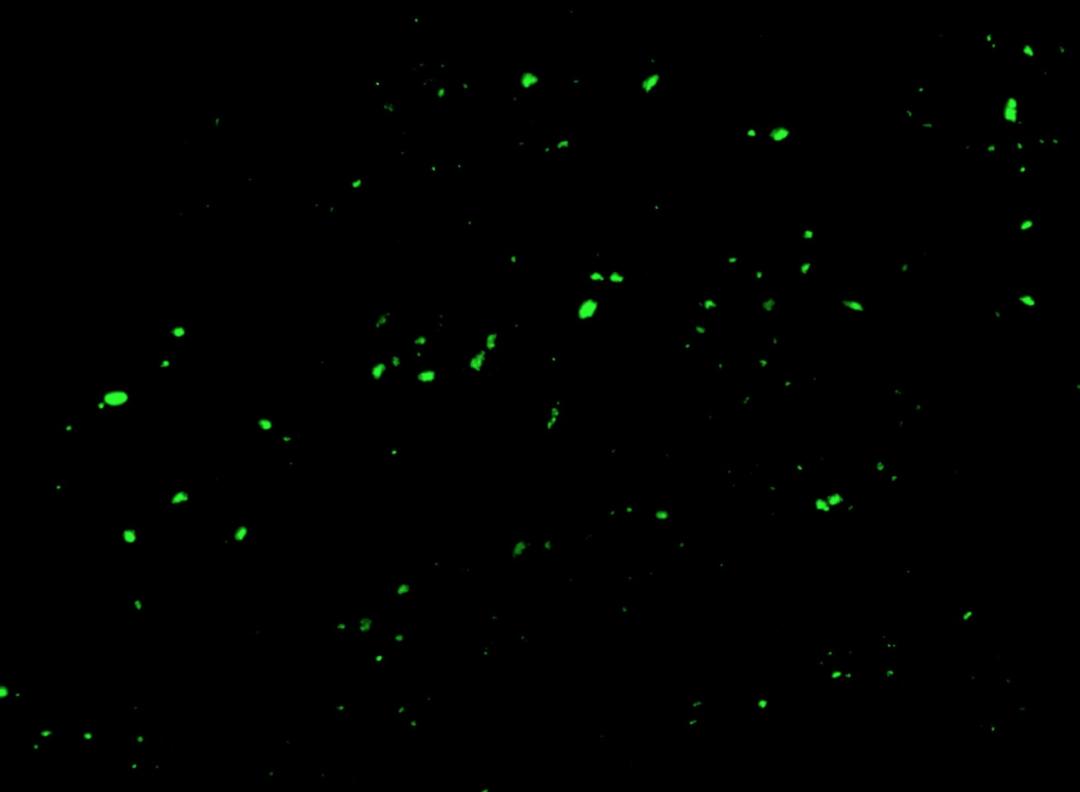

荧光显微镜图像显示健康血液中循环的微血块。 CHANTELLE VENTER 和 RESIA PRETORIUS 的显微照片

检测微凝块需要一种称为荧光显微镜的专门实验室技术。

该过程包括抽血、旋转并添加荧光剂以在荧光显微镜下观察凝块。它不是一般病理实验室中广泛使用的工具。